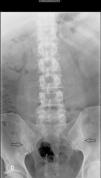

Varón de 44 años con antecedente de ingesta enólica. Acude a la consulta por episodios de mono/oligoartritis en manos y tobillos recurrentes de una semana de duración desde hacía 5 años, y lumbalgia inflamatoria de 10 años de evolución, con dolor alternante en nalgas. No refería otra sintomatología acompañante. A la exploración destacaba la presencia de artritis en carpo derecho, 4.ª y 5.ª IFP mano izquierda junto con nódulos acompañantes. En la analítica se objetivó una uricemia de 13,2mg/dl, VSG 44mm/h (0-20), PCR 15mg/l (<5mg/l) y prueba de Mantoux de 20mm. El resto de parámetros (hemograma, TSH, CPK, factor reumatoide, HLA-B27, anticuerpos anti-citrulinados, inmunoglobulinas, serología de virus hepatotropos, HIV, lues, Brucella, función renal, hepática, sedimento de orina y uricosuria de 24h) fueron normales. Se realizaron radiografías de tórax, manos y pies sin hallazgos patológicos. En la radiografía de columna lumbar (fig. 1) se objetivó una sacroileítis grado II derecha y grado III izquierda. Se completó el estudio con resonancia magnética (RM) de columna lumbar que fue normal y RM de sacroilíacas (fig. 2) donde se objetivaron irregularidades y erosiones en ambas articulaciones sacroilíacas en secuencia T1. En secuencia STIR, se detectó una edema de médula ósea subcondral más acentuado en hueso ilíaco y en la sacra izquierda, y con menor afectación de la sacroilíaca derecha.